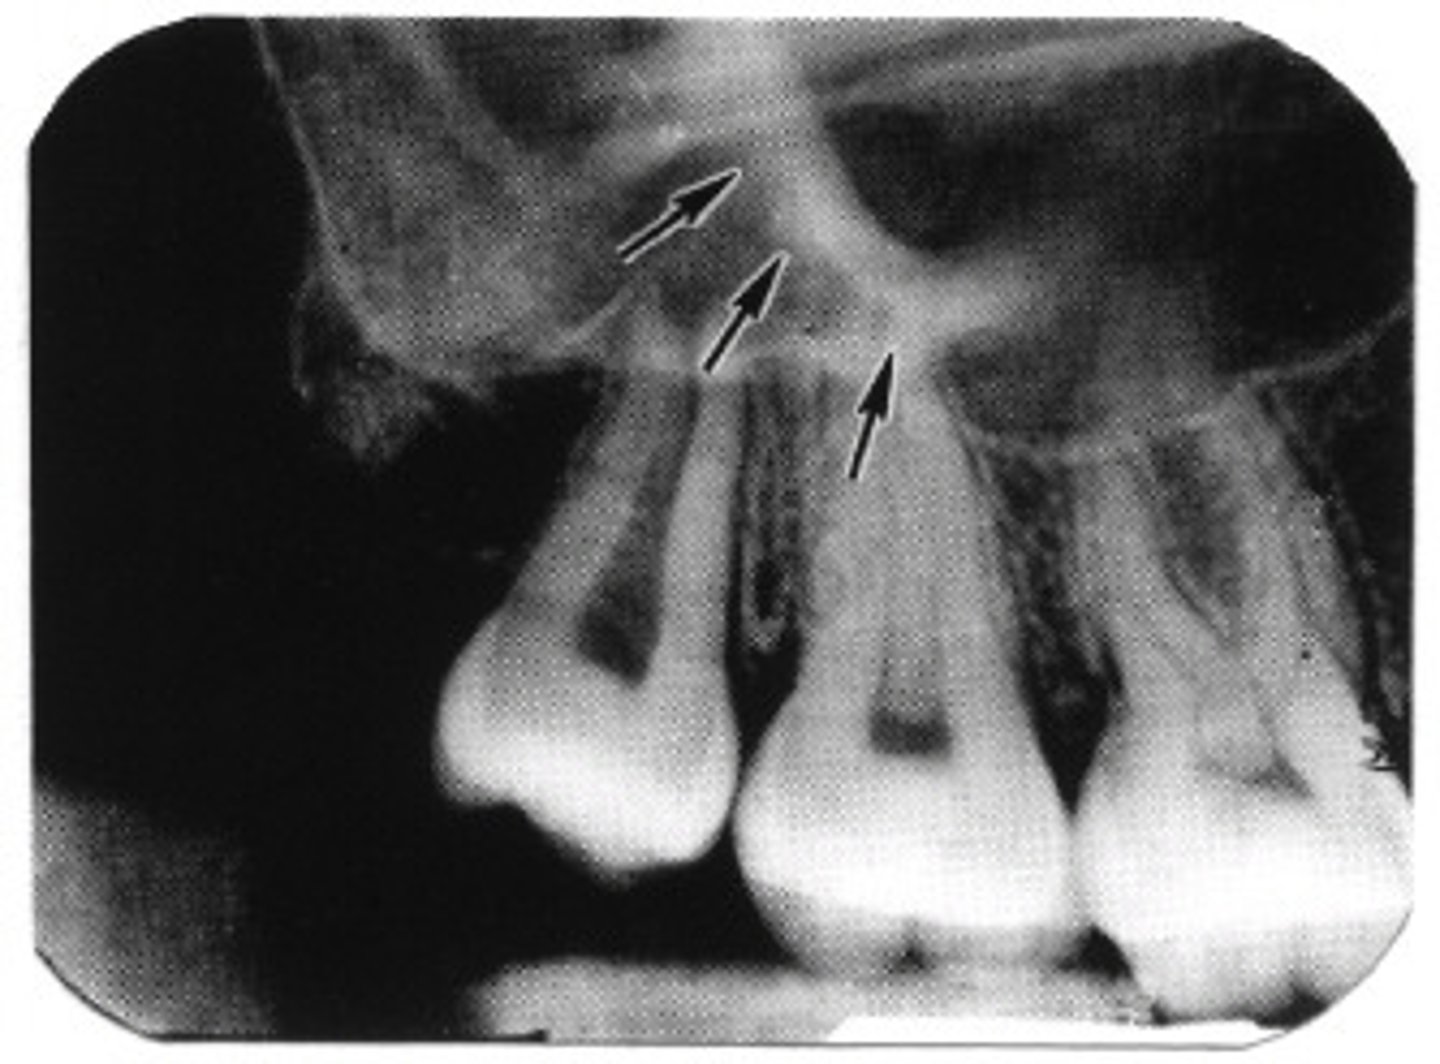

where can you see zygomatic process in a radiograph

apices of max molars

does the maxillary sinus appear radiolucent or radiopaque in a radiograph

radiolucent

does the zygomatic process appear radiolucent or radiopaque in a radiograph

radiopaque